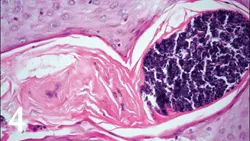

4. Early dermatohistopathologic lesions involve lymphoplasmacytic periductal inflammation, sebaceous gland duct dilation, and follicular keratosis with plugging and dilation (Figure 3). More advanced lesions show evidence of folliculitis (Figure 4), furunculosis, pyogranulomatous sebaceous adenitis, and dermatitis. Staphylococcus spp organisms and Malassezia spp may be present in comedones and surface crusts.

Figure 3. Histopathology of a comedone specimen (

magnification, 100×)